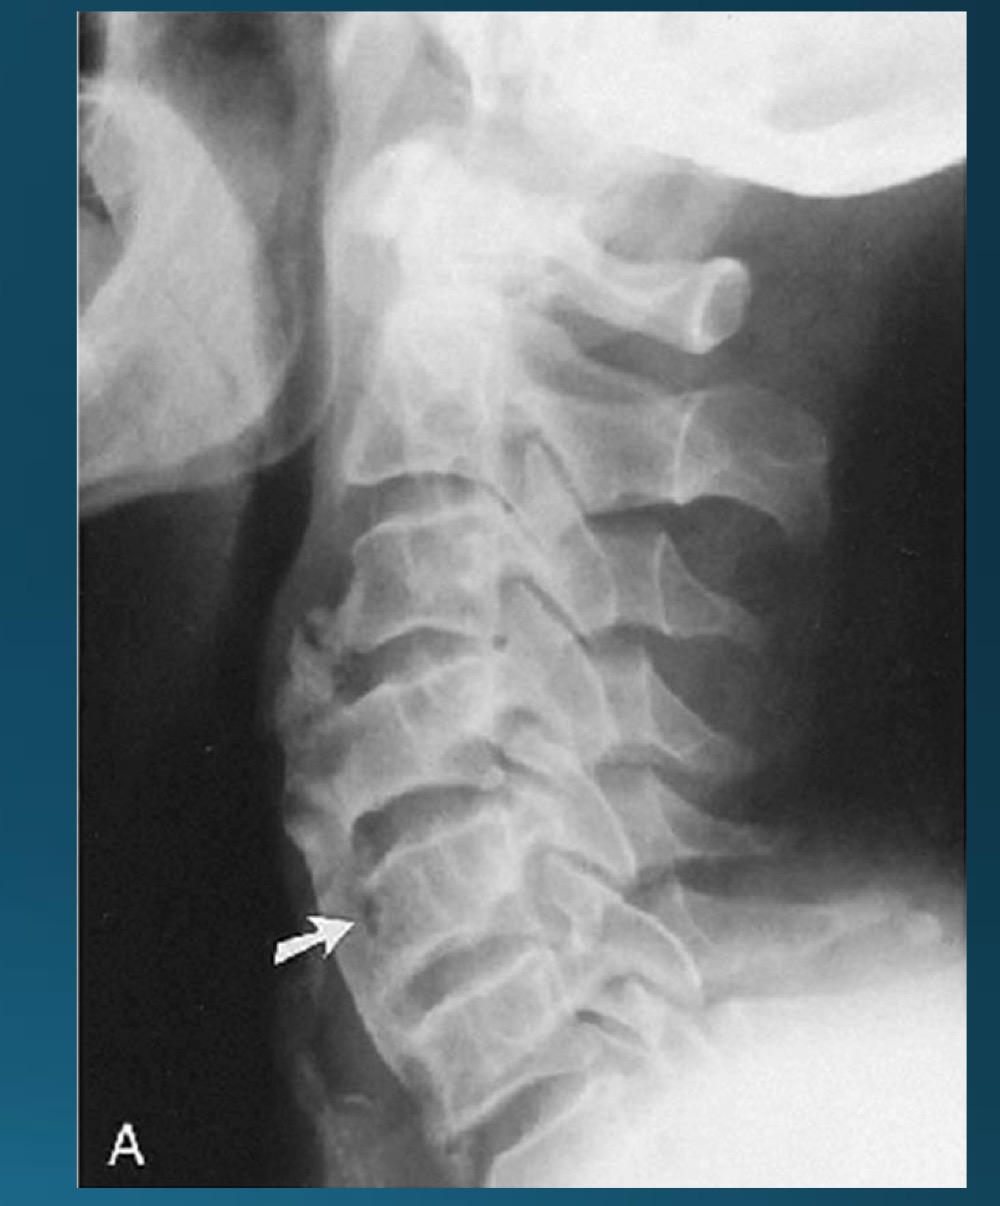

what degenerative joint disease is only found in the cervical spine

uncovertebral joint arthrosis

what are the findings in this image?

what do you call the radiographic feature commonly seen in uncovertebral joint arthrosis

pseudofracture

facet arthrosis